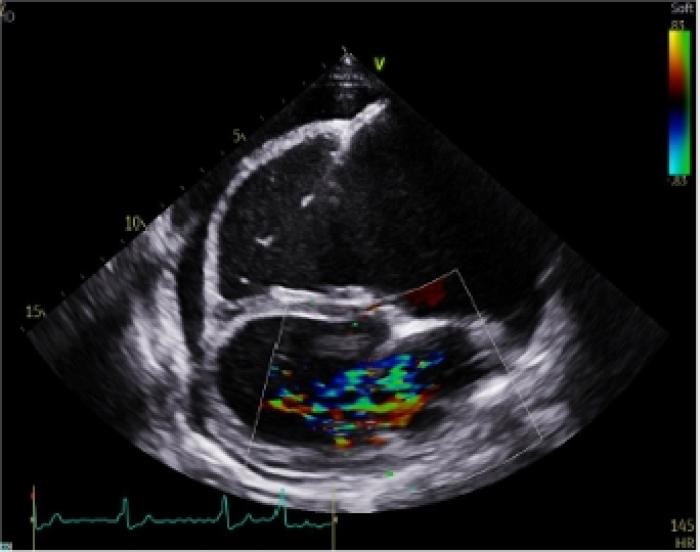

En el examen por Doppler color, se detecta flujo turbulento severo a nivel de la válvula tricúspide (Figura 4A) y moderado en la válvula mitral. A nivel de la válvula pulmonar se detecta una leve insuficiencia, aunque muestra una apariencia normal. Las velocidades aórticas se encuentran por encima del límite normal, con un valor de 2.23 m/s (referencia: <2 m/s). La función sistólica se encuentra disminuida, con una fracción de acortamiento (FA) del 13.77 % (referencia: 28-45 %) y una fracción de eyección (FE) del 29.34 % (referencia: 40-75 %) (Figura 4B).

Figura 4. (A) Examen con Doppler Color de la válvula mitral en un corte paraesternal derecho de cuatro cámaras en el que se aprecia la regurgitación mitral. (B) Modo M a nivel de los ventrículos mediante eje corto por ventana paraesternal derecha.